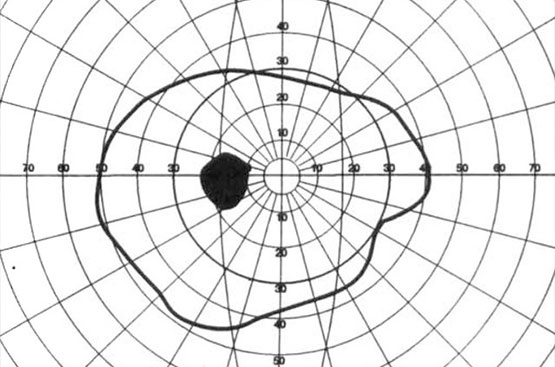

Campo Visivo

Perimetria digitalizzata per la cura del glaucoma e dei difetti campimetrici monoculari e binoculari